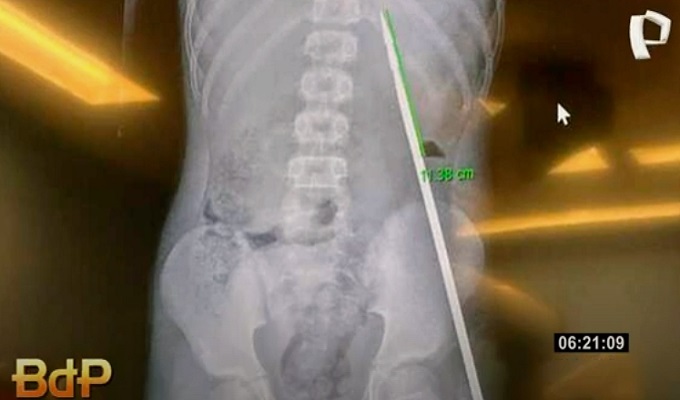

En un impresionante incidente, un joven de la localidad de Santa Rosillo, en la región de San Martín, Tarapoto, sobrevivió a un grave accidente de pesca. Mientras realizaba sus labores cotidianas de pesca, el adolescente accidentalmente se incrustó un arpón en el abdomen. Tras un angustioso traslado de 11 horas, el joven fue operado con éxito en la ciudad de Tarapoto.

El hecho ocurrió cuando el joven estaba pescando con un arpón, herramienta comúnmente utilizada en su localidad para la pesca. Por razones aún desconocidas, el arpón se volvió contra él, incrustándose en su abdomen.

A su llegada, el joven fue atendido de inmediato por los médicos, quienes lograron extraer exitosamente el arpón.